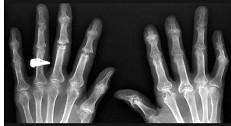

女,52岁,足跟痛,手指运动僵硬,请结合影像图像,选择最可能的诊断 ( )A、骨折B、类风湿关节炎C、骨脓肿D、骨囊肿E、骨质疏松

问题 女,52岁,足跟痛,手指运动僵硬,请结合影像图像,选择最可能的诊断 ( )

选项 A、骨折 B、类风湿关节炎 C、骨脓肿 D、骨囊肿 E、骨质疏松

答案 B